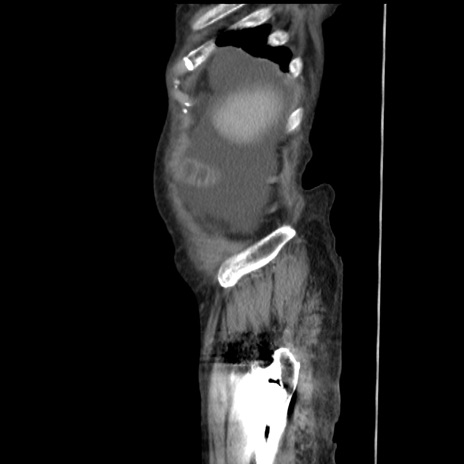

症例31(矢状断像)

【症例】80歳代 女性

【主訴】腹部膨満感

【現病歴】他院にて肝硬変にてフォロー中。1週間前から便秘、腹部膨満感、臍部腫瘤あり受診となる。

【既往歴】肝硬変

【身体所見】腹部膨隆あり、皮膚変化なし、疼痛なし。

【データ】WBC 4600、CRP 0.25